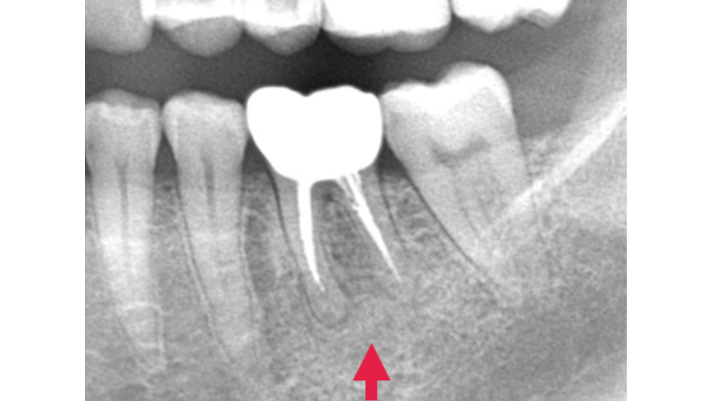

治療前

患者様は「何度も腫れる」「根の治療を繰り返している」とのお悩みで来院されました。診査の結果、歯の根の先に膿の袋(根尖病変)が確認され、過去の治療で細菌が十分に取り除けていない可能性が考えられました。そこで、ラバーダムを使用して治療部位への細菌の侵入を防ぎながら、拡大視野下で精密な根管治療の再治療を行い、感染源の徹底的な除去を行いました。

| 主訴 | 右下が腫れて痛い |

|---|---|

| 治療期間 | 1ヶ月 |

| 治療費 | 保険適用 |

| 治療内容 | レントゲンで確認すると、根尖病変が認められ根管治療を行いました。 |

| 治療のリスク | 再発が起きる場合は、外科処置を追加で必要なケースがあります。 |